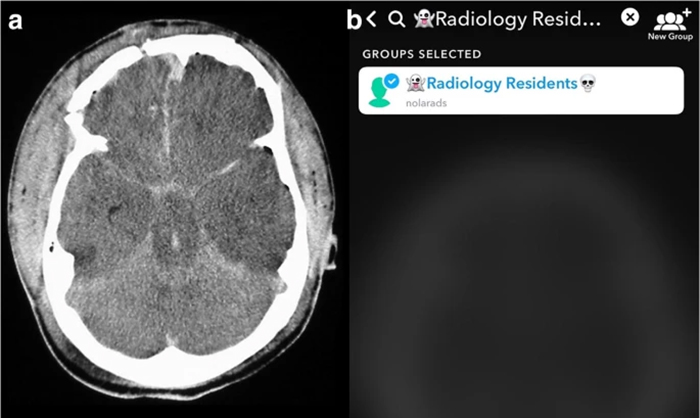

The team compared image analysis and interpretation by radiology residents using Snapchat on smartphones with conventional analysis on a single screen in the resident conference room.

The team chose Snapchat, a social media app allowing communication via video and digital images with text messaging functionality, not only because of its popularity with young adults, but most importantly because unlike other image based social media platforms, Snapchat allows for the timing of image visibility by users. The ability to specify the length of time an image is visible to a user (or trainee in this scenario) in rendering an image-based diagnosis creates an intriguing potential for innovation in radiologic curricula, particularly as it relates to assigning a metric to diagnostic performance.

Over a four-week period, LSU Health New Orleans radiology residents, who are all millennials, were shown five emergent radiologic cases using Snapchat and five cases of similar content and duration on a classroom projector. All images depicted diagnoses requiring immediate communication to ordering physicians. Performance was scored 0–2 (0 = complete miss, 1 = major finding, but missed the diagnosis, 2 = correct diagnosis) by two attending radiologists in consensus.

“All residents performed better on Snapchat each week,” says Dr. Spieler, who is also an Associate Professor of Radiology, Internal Medicine, Urology, & Cell Biology and Anatomy at LSU Health New Orleans. “Their accuracy rate was higher using Snapchat than a traditional classroom screen.”

The authors maintain that new challenges presented by the COVID-19 pandemic underscore the need to alter curricular landscapes through innovative teaching methods and connectivity with students and residents. Smartphones and mobile devices are used daily in hospitals in patient care. The comfort level with this technology is high, which simplifies its integration into graduate medical education. Radiology is a specialty particularly suited to visual social media platforms, and it is only natural that the technologically bound craft of radiology continues to push this medium in innovative ways.